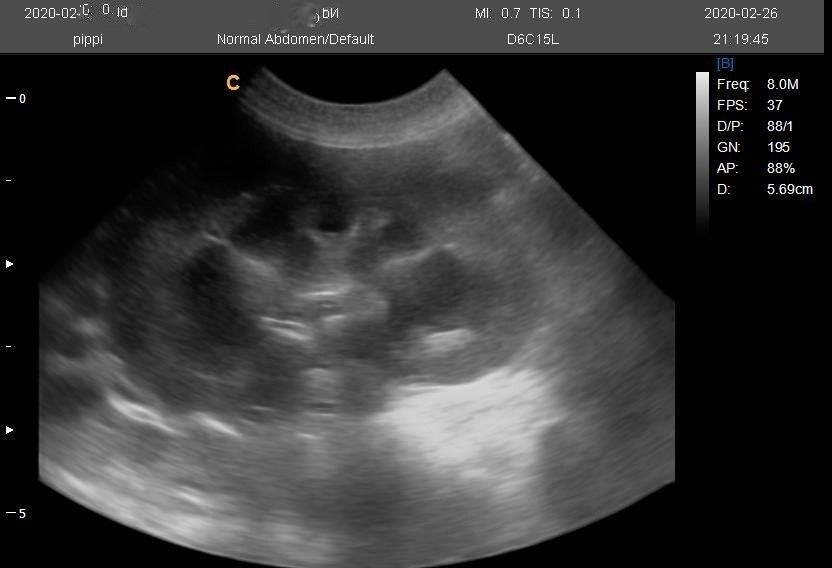

The patient button, probe settings, frequency, depth, focal zone, overall gain and TGC buttons are labelled well and are easily found, as are freeze and save. Images are easily transferred to USB, but one problem I have had with this machine is it doesn’t transfer cineloops. Another more minor bug bear with this machine has been when I annotate an image I have to press the first letter I’m writing twice, as the first time I press it starts to register that it is writing. This means I have labelled many images as “Ladder” instead of “Bladder”! I am happy with the image quality, although occasionally it can appear brighter than other ultrasound machines. I’ve used this machine with the linear probe D7L40L (4-13MHz) and the microconvex – D6CI5L A (4-12MHz) in cats and dogs for abdominal scans and basic echocardiography scans. It has coped with these challenges well. These frequency ranges are great for covering large and small dogs and cats.

I’ve included an image I’ve taken on this machine – but to be fair it was on my bouncy 8 month old puppy who has just started in the ultrasound business.

Images from the Q5 Vet Portable